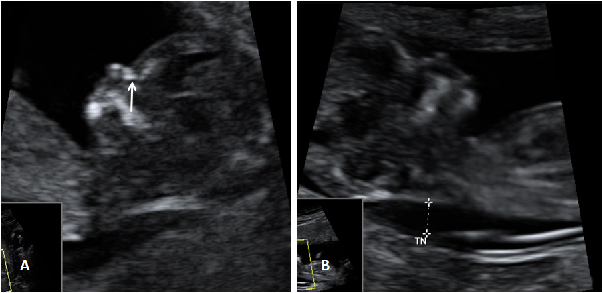

La ecografía en 4D (vídeo) no deja lugar a dudas. Se trata de un embarazo de siameses de 11 semanas de gestación, que están unidos por la zona abdominal, ya que comparten una pequeña parte de hígado. La movilidad de los bebés es reducida, como vemos en las imágenes, debido a la unión de sus cuerpos. Uno de los hermanos (el de la derecha) mueve la cabeza hacia atrás, mientras las piernas se entrecruzan. Los especialistas siguen este tipo gestaciones muy de cerca y valoran la separación quirúrgica de los bebés, una vez que se produce el parto.